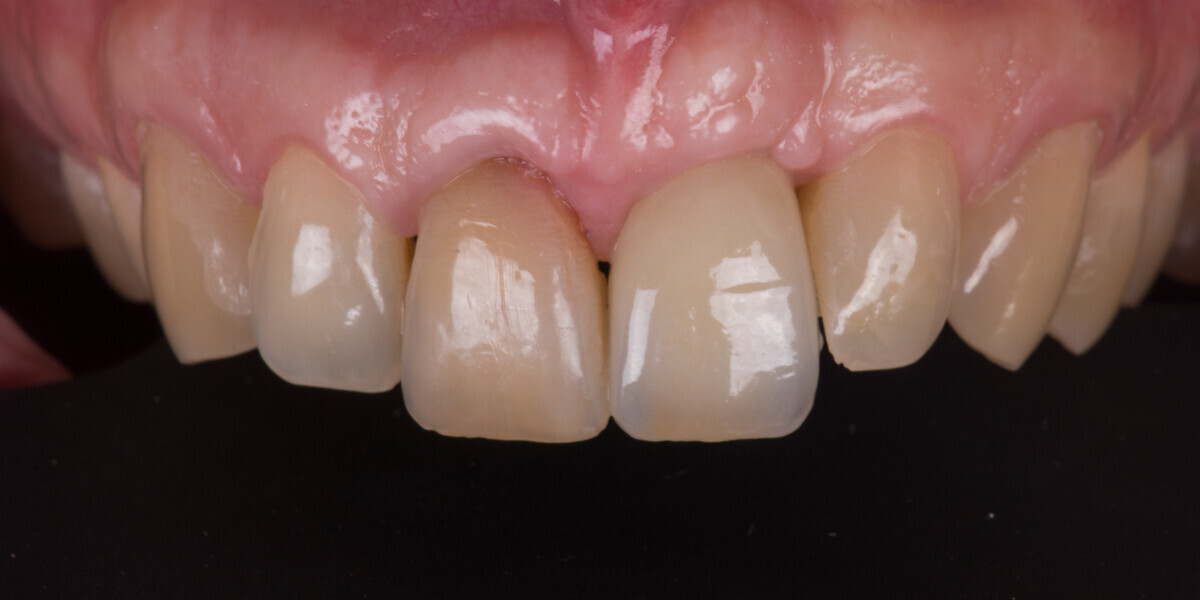

Immediate placement and restoration of a Straumann BLX implant replacing maxillary incisors